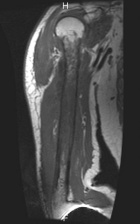

58 year old male with seven week history of increasing right shoulder, arm, and elbow pain and swelling

Zoom image: Radiological image Radiological image.